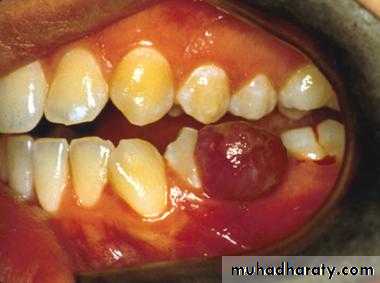

pyogenic granuloma

• Is a benign, elevated, and capillary-rich lesionIs, soft, red or purple mass on the lips, interdental papilla, or buccal mucosa .• It may occur in the skin.

• The cause is thought to be local irritation, hormonal factor or trauma.

• When located at the gingiva of pregnant women, the term pregnancy tumor may be used.

pyogenic granuloma• An oral pyogenic granuloma most frequently involves the gingiva.

• The lower lip and the dorsal surface of the tongue are rather common sites as well.• The lesion is usually pedunculated or sessile, and the surface is often ulcerated.

• The size of the lesion's diameter may vary from 0.5 to 2 cm or more.

• Surgery is the management of choice. Recurrence rare.